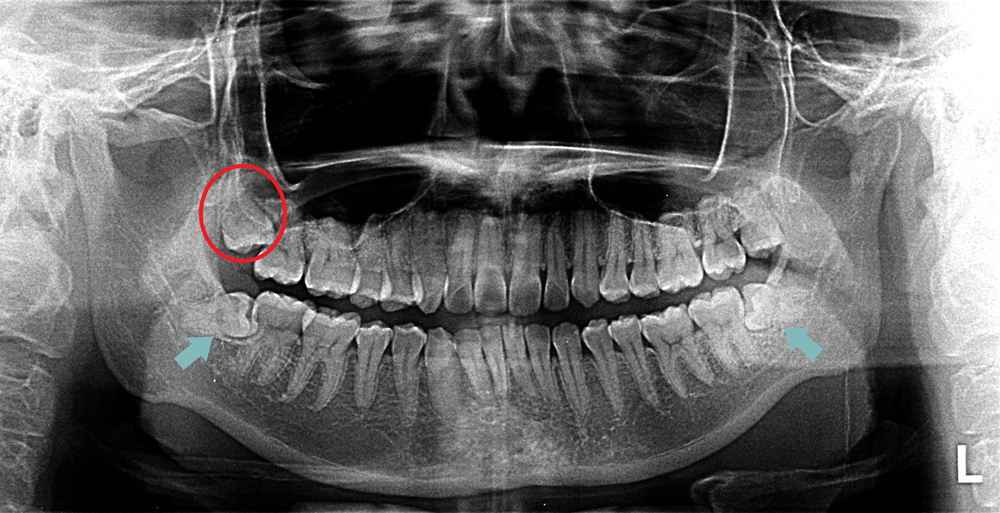

www.shutterstock.comImpacted Wisdom Tooth, Panoral X-ray - Stock Image - C015/2820

www.shutterstock.comImpacted Wisdom Tooth, Panoral X-ray - Stock Image - C015/2820

www.sciencephoto.comwisdom ray tooth impacted

www.sciencephoto.comwisdom ray tooth impacted

www.alamy.comImpacted Wisdom Teeth, X-ray - Stock Image - M782/0249 - Science Photo

www.alamy.comImpacted Wisdom Teeth, X-ray - Stock Image - M782/0249 - Science Photo

www.sciencephoto.comwisdom teeth impacted ray stock

www.sciencephoto.comwisdom teeth impacted ray stock